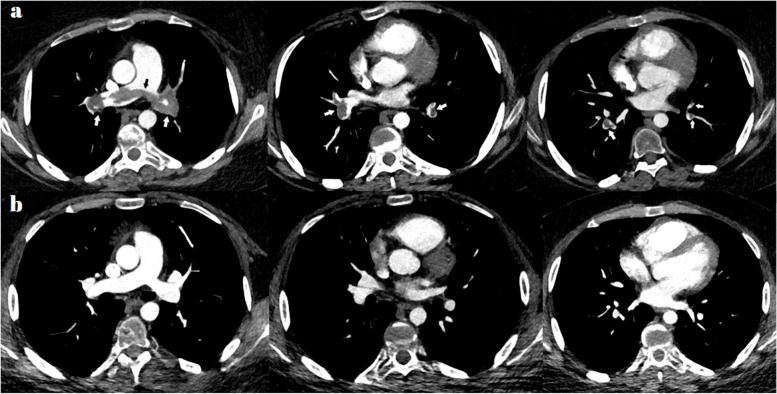

背景:儿童嗜酸性肉芽肿病合并多血管炎(EGPA)患者发生动脉和静脉血栓栓塞(AVTE)的风险增加。虽然AVTE的确切机制尚不清楚,但嗜酸性粒细胞在AVTE中起着关键作用。目前的指南缺乏基于证据的建议,特别是关于这种疾病的抗凝血和抗血小板治疗。在此,我们记录了一位患有深静脉血栓形成的儿童EGPA患者,在复发期间表现为大量肺血栓栓塞,接受免疫抑制和抗凝治疗,以提高临床医生的认识。此外,我们进行了文献综述,以突出儿科AVTE的各个方面。此外,我们评估了文献综述中确定的患者的管理策略,并总结了目前关于儿童EGPA合并AVTE患者的实践指南,为临床医生提供处理这一具有挑战性的并发症的建议。结论:大多数AVTE事件发生在疾病高活动期。值得注意的是,EGPA合并VTE的患者经常出现由于消耗而导致的血小板减少,这一发现在疾病恶化期间通常不会出现。静脉血栓形成通常需要抗凝和免疫抑制治疗。虽然我们的回顾表明AVTE预后良好,但报告的病例数量少,使我们无法得出明确的结论。除了研究抗凝和抗血小板治疗的作用外,未来的研究应探索mepolizumab和其他嗜酸性粒细胞靶向治疗对AVTE的疗效。

Main body: Current guidelines lack evidence-based recommendations, particularly concerning anticoagulant and antiplatelet treatments for this condition. Herein, we document a pediatric EGPA patient with deep venous thrombosis presenting with massive pulmonary thromboembolism during a relapse, treated with immunosuppressive and anticoagulant therapy to raise awareness among clinicians. Additionally, we performed a literature review to highlight various aspects of pediatric AVTE. Moreover, we evaluated the management strategies employed for the patients identified in the literature review and summarized the current practice guidelines regarding pediatric EGPA patients with AVTE to provide recommendations to clinicians on the management of this challenging complication.